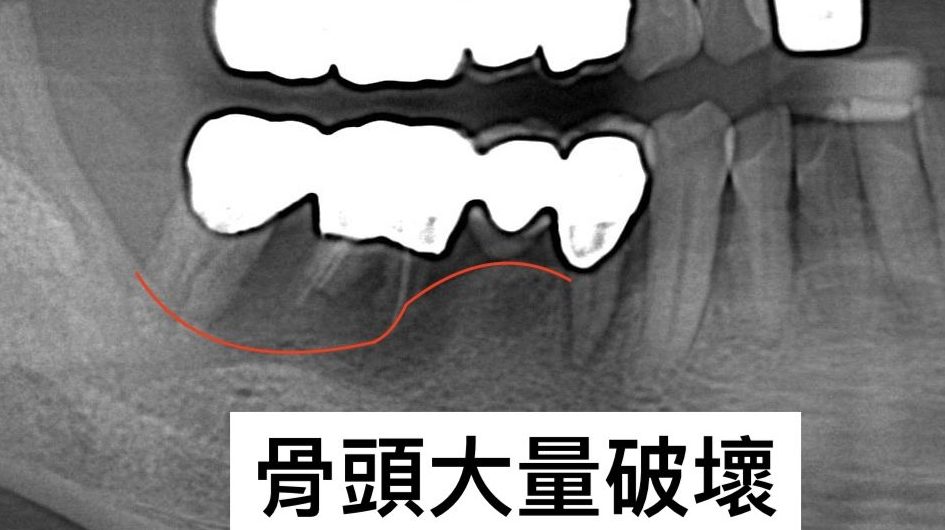

透過3D電腦斷層與口腔掃描,先全面檢查牙齒與骨頭狀況,並建立3D模型。醫師會以此確認所需補骨範圍、預先模擬手術效果,並決定適合的手術方式。